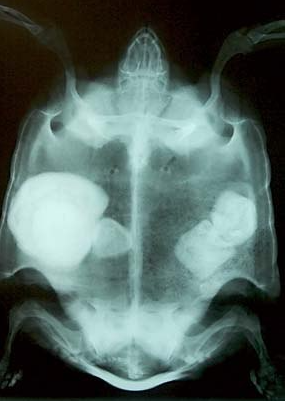

Черепахе нужно сделать как минимум 2 проекции рентгена, чтобы посмотреть лёгкие и область жкт:

image.thumb.png.e9f96d3db3d217b9c98af7565ea3e8c9.pngimage.png.1ba8c1ef321679c2788509cadb4fef3b.pngи

дальнейшие действия зависят от того что покажет рентген